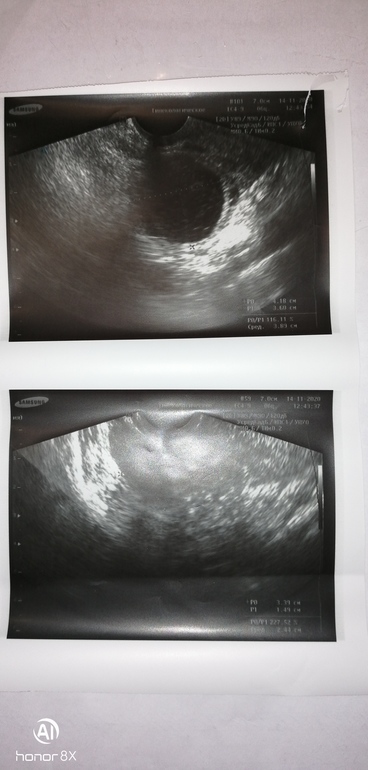

вот узи

Ооо у Вас шикарное у меня реально маленькое

Дай Бог!🙏😏но весь инет перерыла с таким желтым телом не может быть. Но на ББ видела с 16 и 17 Б

И кстати эндометрий у вас хороший, у меня всего 10мм

Моя сказала что отличное прекрасное жт...но я понимаю,что нет. Еще и овуляция в левом как мне надо,1 ж труба😔а почему-то пролет

Эндометрий не однослойный, а однородный, это норма. Трехслойным он должен быть в первой фазе. А размер ЖТ никак не влияет на количество вырабатываемого прогестерона

Угасание ЖТ определяют по степени визуализации и ЦДК (кровотоку по контуру), в заключении не написано по этому поводу ничего, поэтому сказать нельзя. По эндометрию тоже можно определить, когда пойдут месячные (линия смыкания лепестков перестаёт визуализироваться)